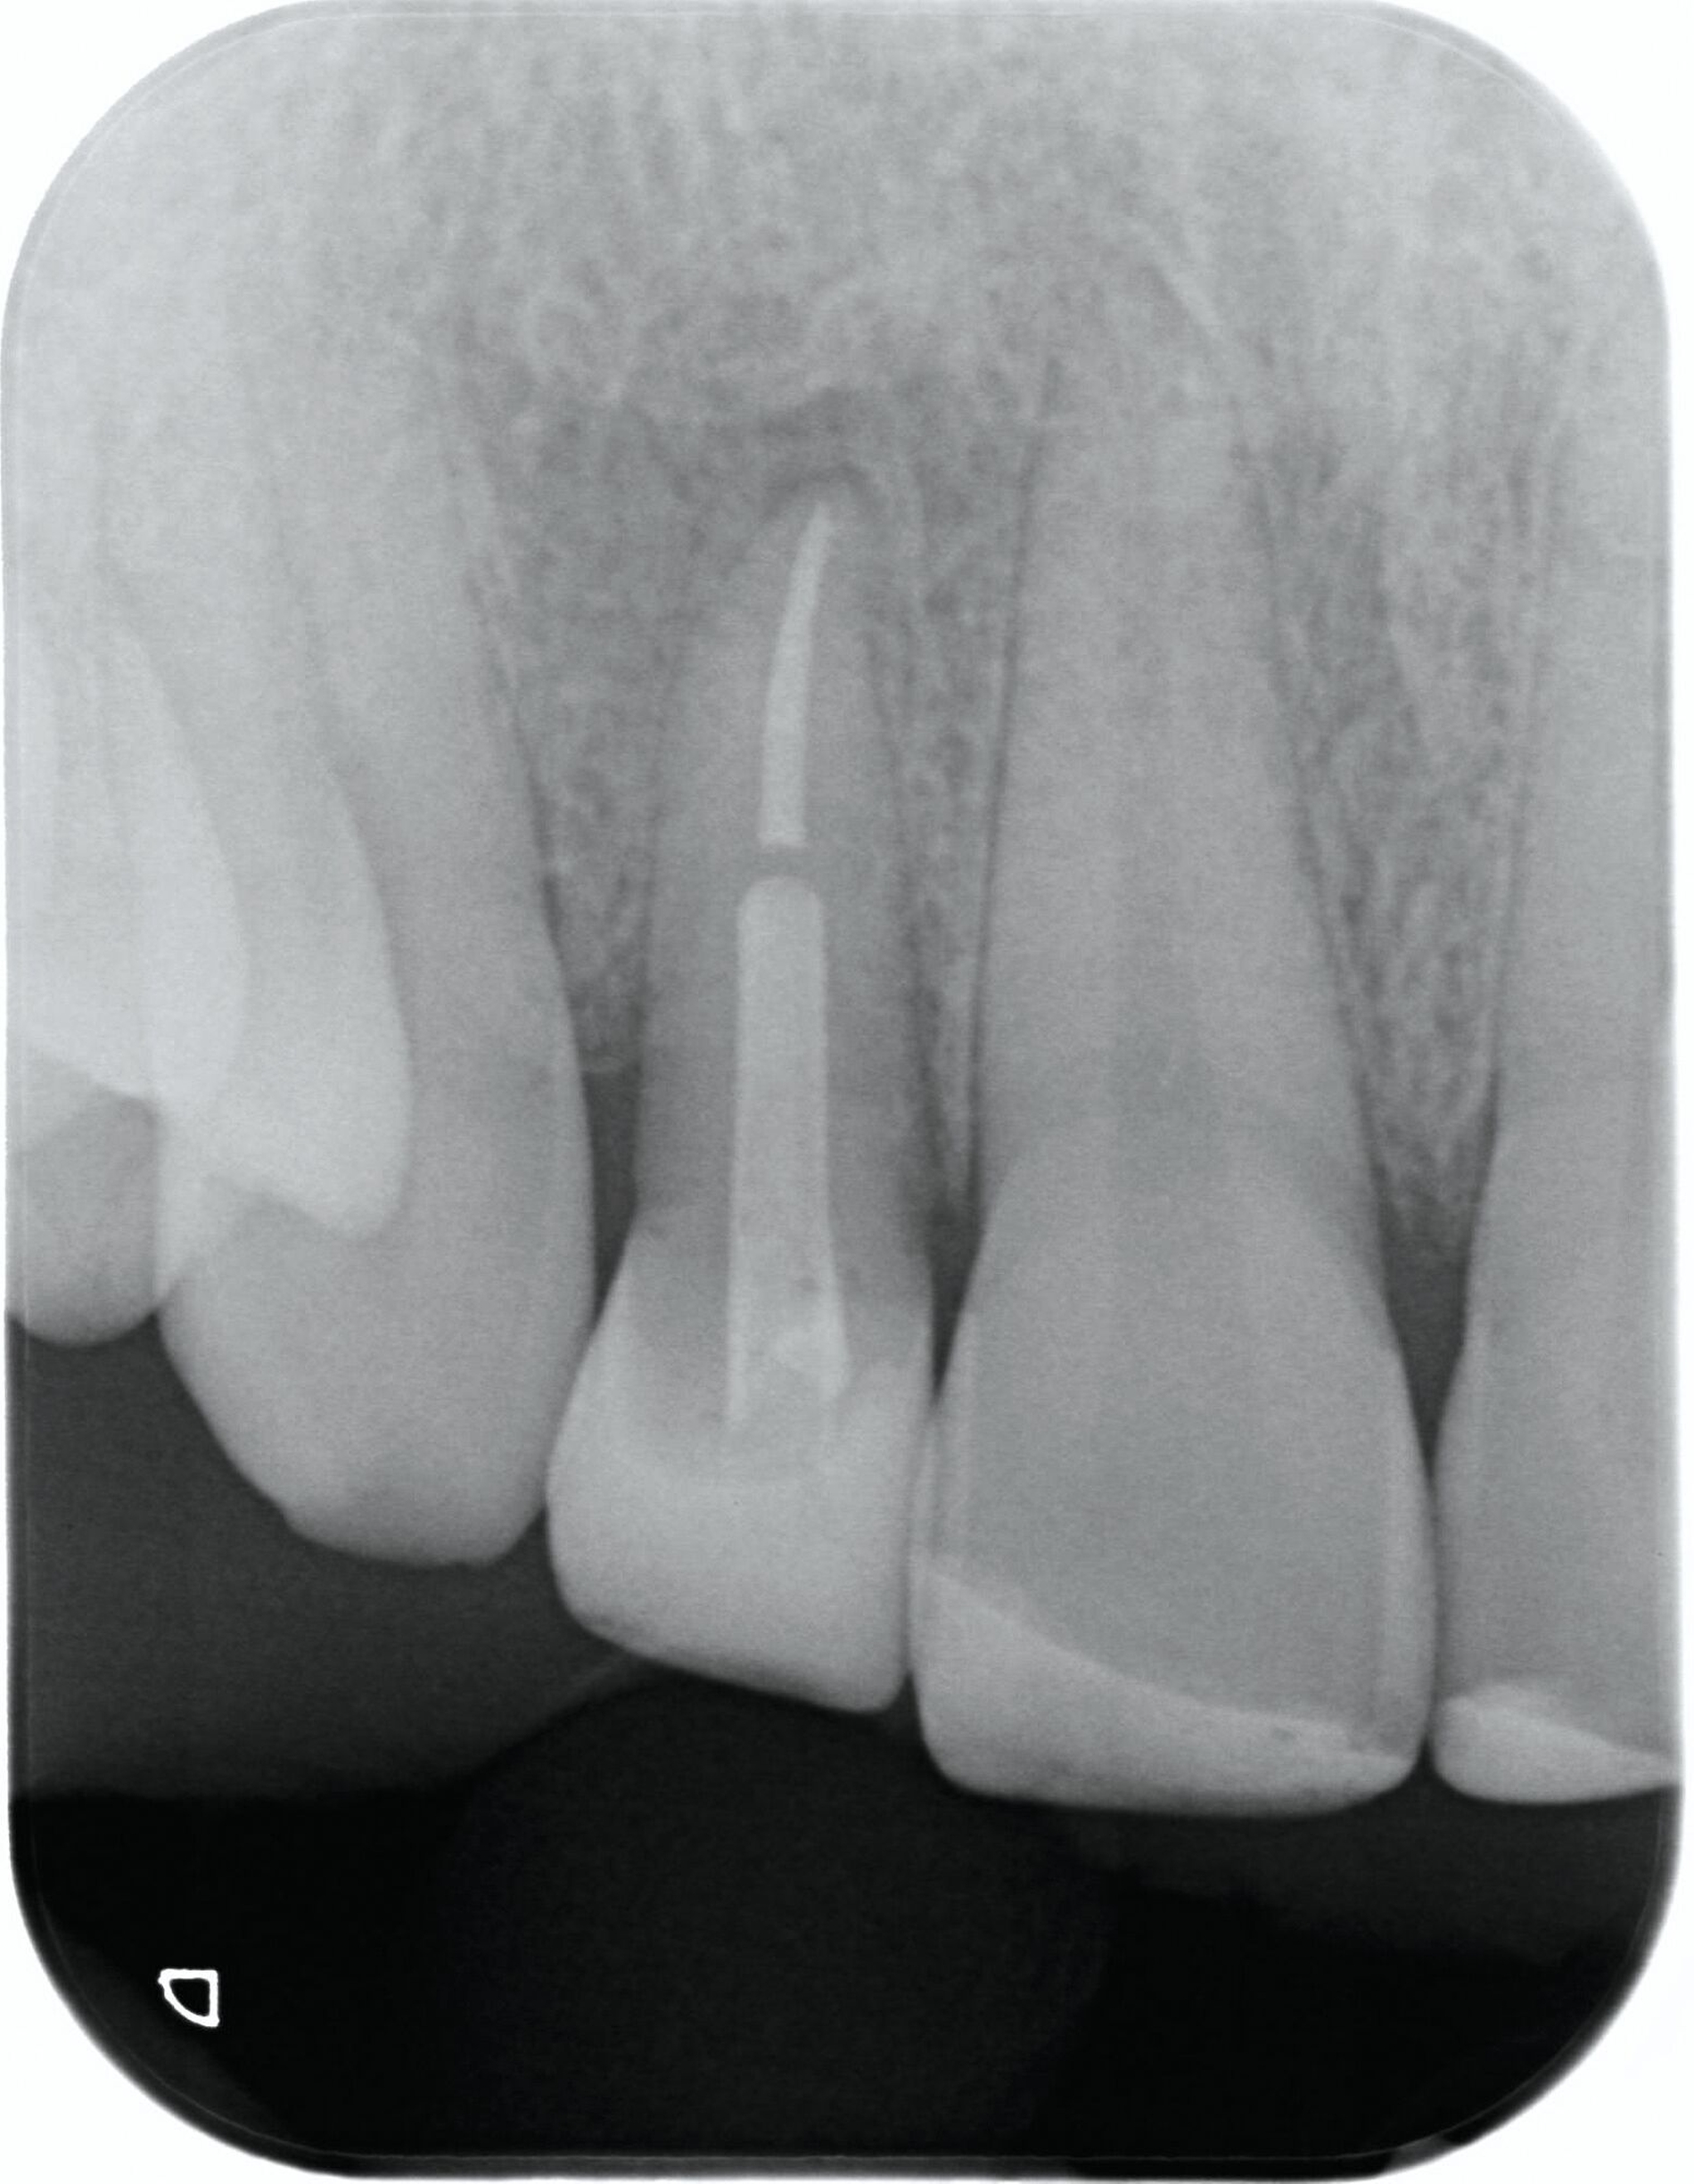

Nach einem vollständigen Zahnverlust oder auch nach einer erfolgten Dekoronation ankylosierter Zähne bietet sich insbesondere bei jungen Patienten die Versorgung mit einer Adhäsivbrücke an. Die einflügelige Adhäsivbrücke stellt eine minimalinvasive Möglichkeit zur Versorgung der Lücke bei Schneidezähnen dar (Abbildung 3). Für diese Versorgungsform liegen sehr gute Langzeitüberlebensraten von über 98 Prozent vor [Kern et al., 2017]. Einflügelige Adhäsivbrücken haben im Vergleich zu zweiflügeligen Adhäsivbrücken eine signifikant höhere Überlebensrate [Thoma et al., 2017].